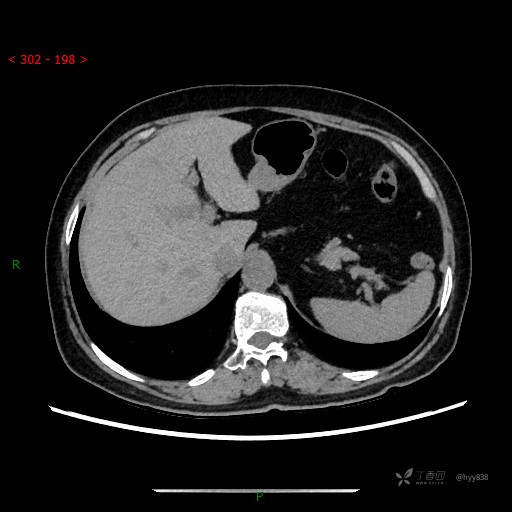

静脉期